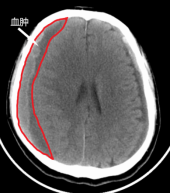

慢性硬膜下血肿是颅内硬膜下腔(硬脑膜与蛛网膜之间的腔隙)的陈旧性血肿,多见于老年人,常在头部创伤3周以后形成。

如老人有头部外伤史,并且出现了以上临床表现,行头部CT检查即可作出诊断。